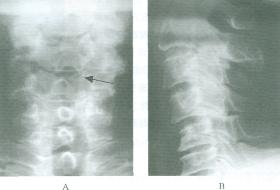

(5)頸椎受累時,關節突被侵蝕關節間隙狹窄最終融合但椎間盤本身未被波及。常有寰樞椎半脫位

(6)骨骺的正常生長受到干擾或提前成熟,使骨過度生長;或提前與骨幹融合,使生長過早停止健康搜尋,導致肢體不等長骨骺膨大下頜短小等畸形。